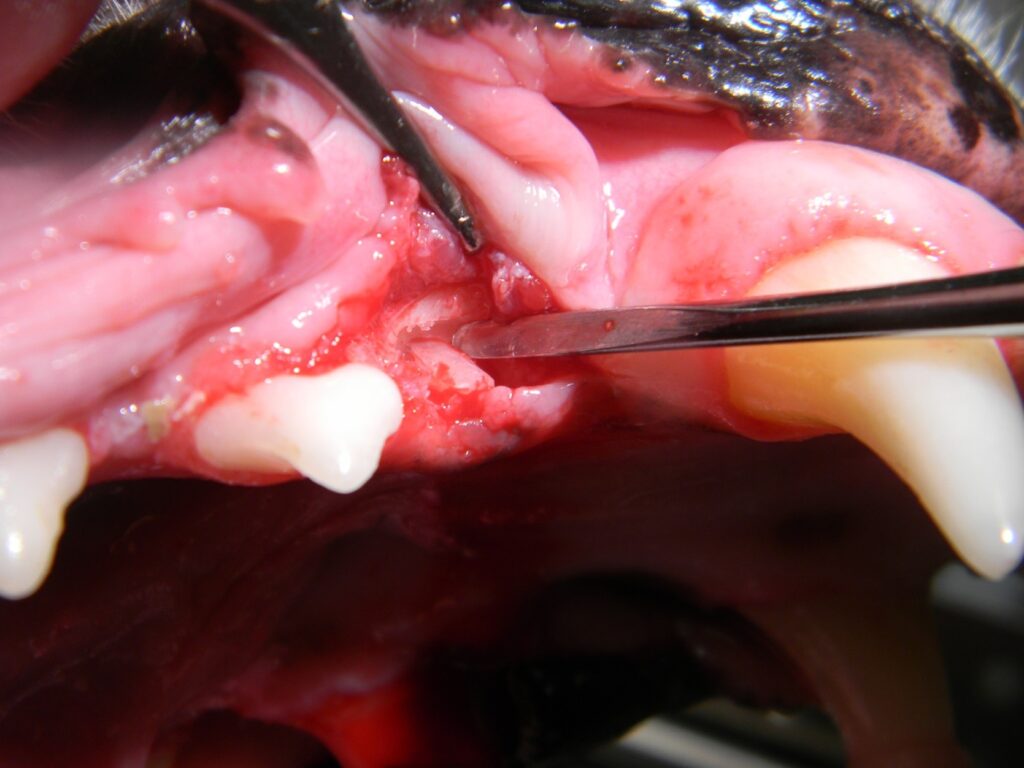

The length of the incision should be determined based on the anticipated amount of exposure required to retrieve the fragments. Following flap creation, buccal cortical bone is removed with a carbide bur to a point somewhat below the most coronal aspect of the remaining root. (Figure 3)

If necessary, the bone can be removed 360 degrees around the tooth; however, this author attempts to avoid this aggressive approach. Once the root (s) can be visualized (Figure 4), careful elevation with small, sharp elevators is initiated. (Figure 5)

Once the root is mobile, it can be extracted normally. After the root is extracted (Figure 6), the bone is smoothed and the defect closed. (Figure 7)